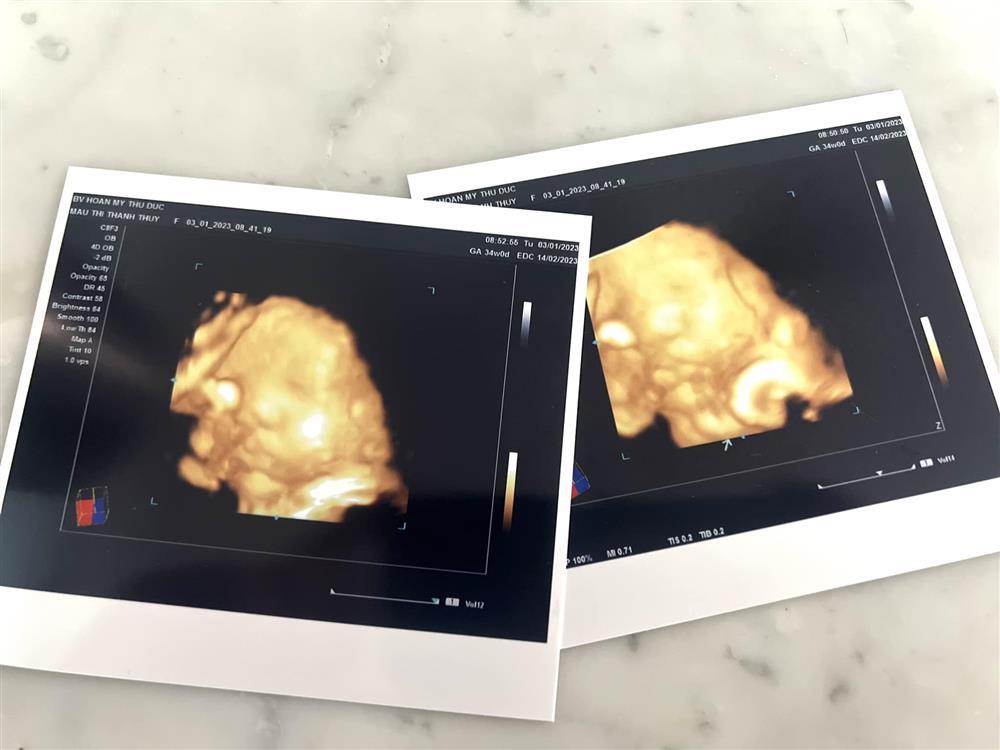

Mở đầu tin showbiz Việt là chia sẻ của Mâu Thủy: "Chào Mâu con, 34 tuần được 3kg rồi, mẹ cũng tăng 17kg rồi còn gì. Lúc đầu dự tính sinh thường, để khi nào con muốn ra thì ra. Nhưng nếu trên đà này thì chắc cho bác sĩ quyết định quá, nhưng không sao, mẹ con đều khoẻ mạnh là được...

... Nhưng không may sao tối qua đau bụng lúc 12h khuya, phải đi vào bệnh viện gấp, sau khi chuẩn đoán đo nhịp tim thai biết là xuất hiện những cơn gò cao độ, có thể sinh sớm hơn dự tính, lo lắng nóng đầu là phải sinh luôn trong đêm. Nhưng may mắn cũng không sao, chỉ là tín hiệu cơn gò giả, khúc này mấy mẹ bỉm mới hiểu. Thế là 3 giờ sáng xuất viện về, hủy luôn buổi chụp hình ngày mai. Ông kia thì nói gần sinh rồi, em ở nhà giùm anh, còn mình thì ở nhà chùn chân. Nhưng thôi còn hơn 1 tháng..., đi đâu ổng hộ tống tui đi giùm là được, yêu yêu".